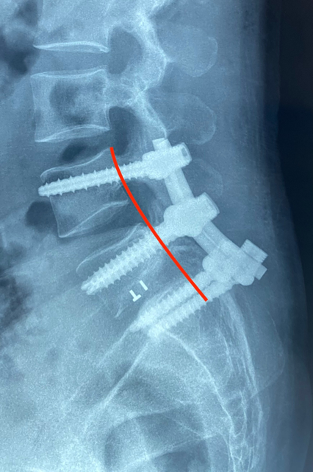

Ths.Bs Trần Đức Duy Trí, một chuyên gia trong lĩnh vực phẫu thuật cột sống tại Bệnh viện Hoàn Mỹ ITO Đồng Nai đã thực hiện ca phẫu thuật với sự tận tâm cùng ekip phẫu thuật. Đối mặt với những thách thức nguy cơ cao về liệt sau phẫu thuật do tổn thương nghiêm trọng tại đốt sống L5, ca phẫu thuật kéo dài hơn 3 giờ, Ths.Bs Duy Trí đã tiến hành bắt vít cuống cung cố định nẹp dọc từ L4-S1 và nắn trượt đốt sống, giải áp rễ và bao màng cứng. Nhờ sự kết hợp giữa tài năng của đội ngũ bác sĩ và sự hỗ trợ của máy C-Arm trong mổ, ca phẫu thuật đã đạt được thành công ngoài sự mong đợi. Chỉ sau một ngày, người bệnh đã có thể di chuyển đi lại và giảm đau vùng lưng và chân.

X-Quang trước và sau phẫu thuật

Ths.Bs Duy Trí chia sẻ: “Trượt thân sống độ IV rất nguy hiểm, đây là một ca phẫu thuật rất khó và phức tạp nguy cơ tổn thương rễ thần kinh trong khi mổ cao. Do trượt độ IV nên các cấu trúc giải phẫu bị biến đổi nhiều nên việc bắt vít cuống cung cũng có nhiều khó khăn. Mỗi ngày, chúng tôi rất hạnh phúc và tự hào khi thấy người bệnh của chúng tôi hồi phục và trở lại cuộc sống bình thường.”